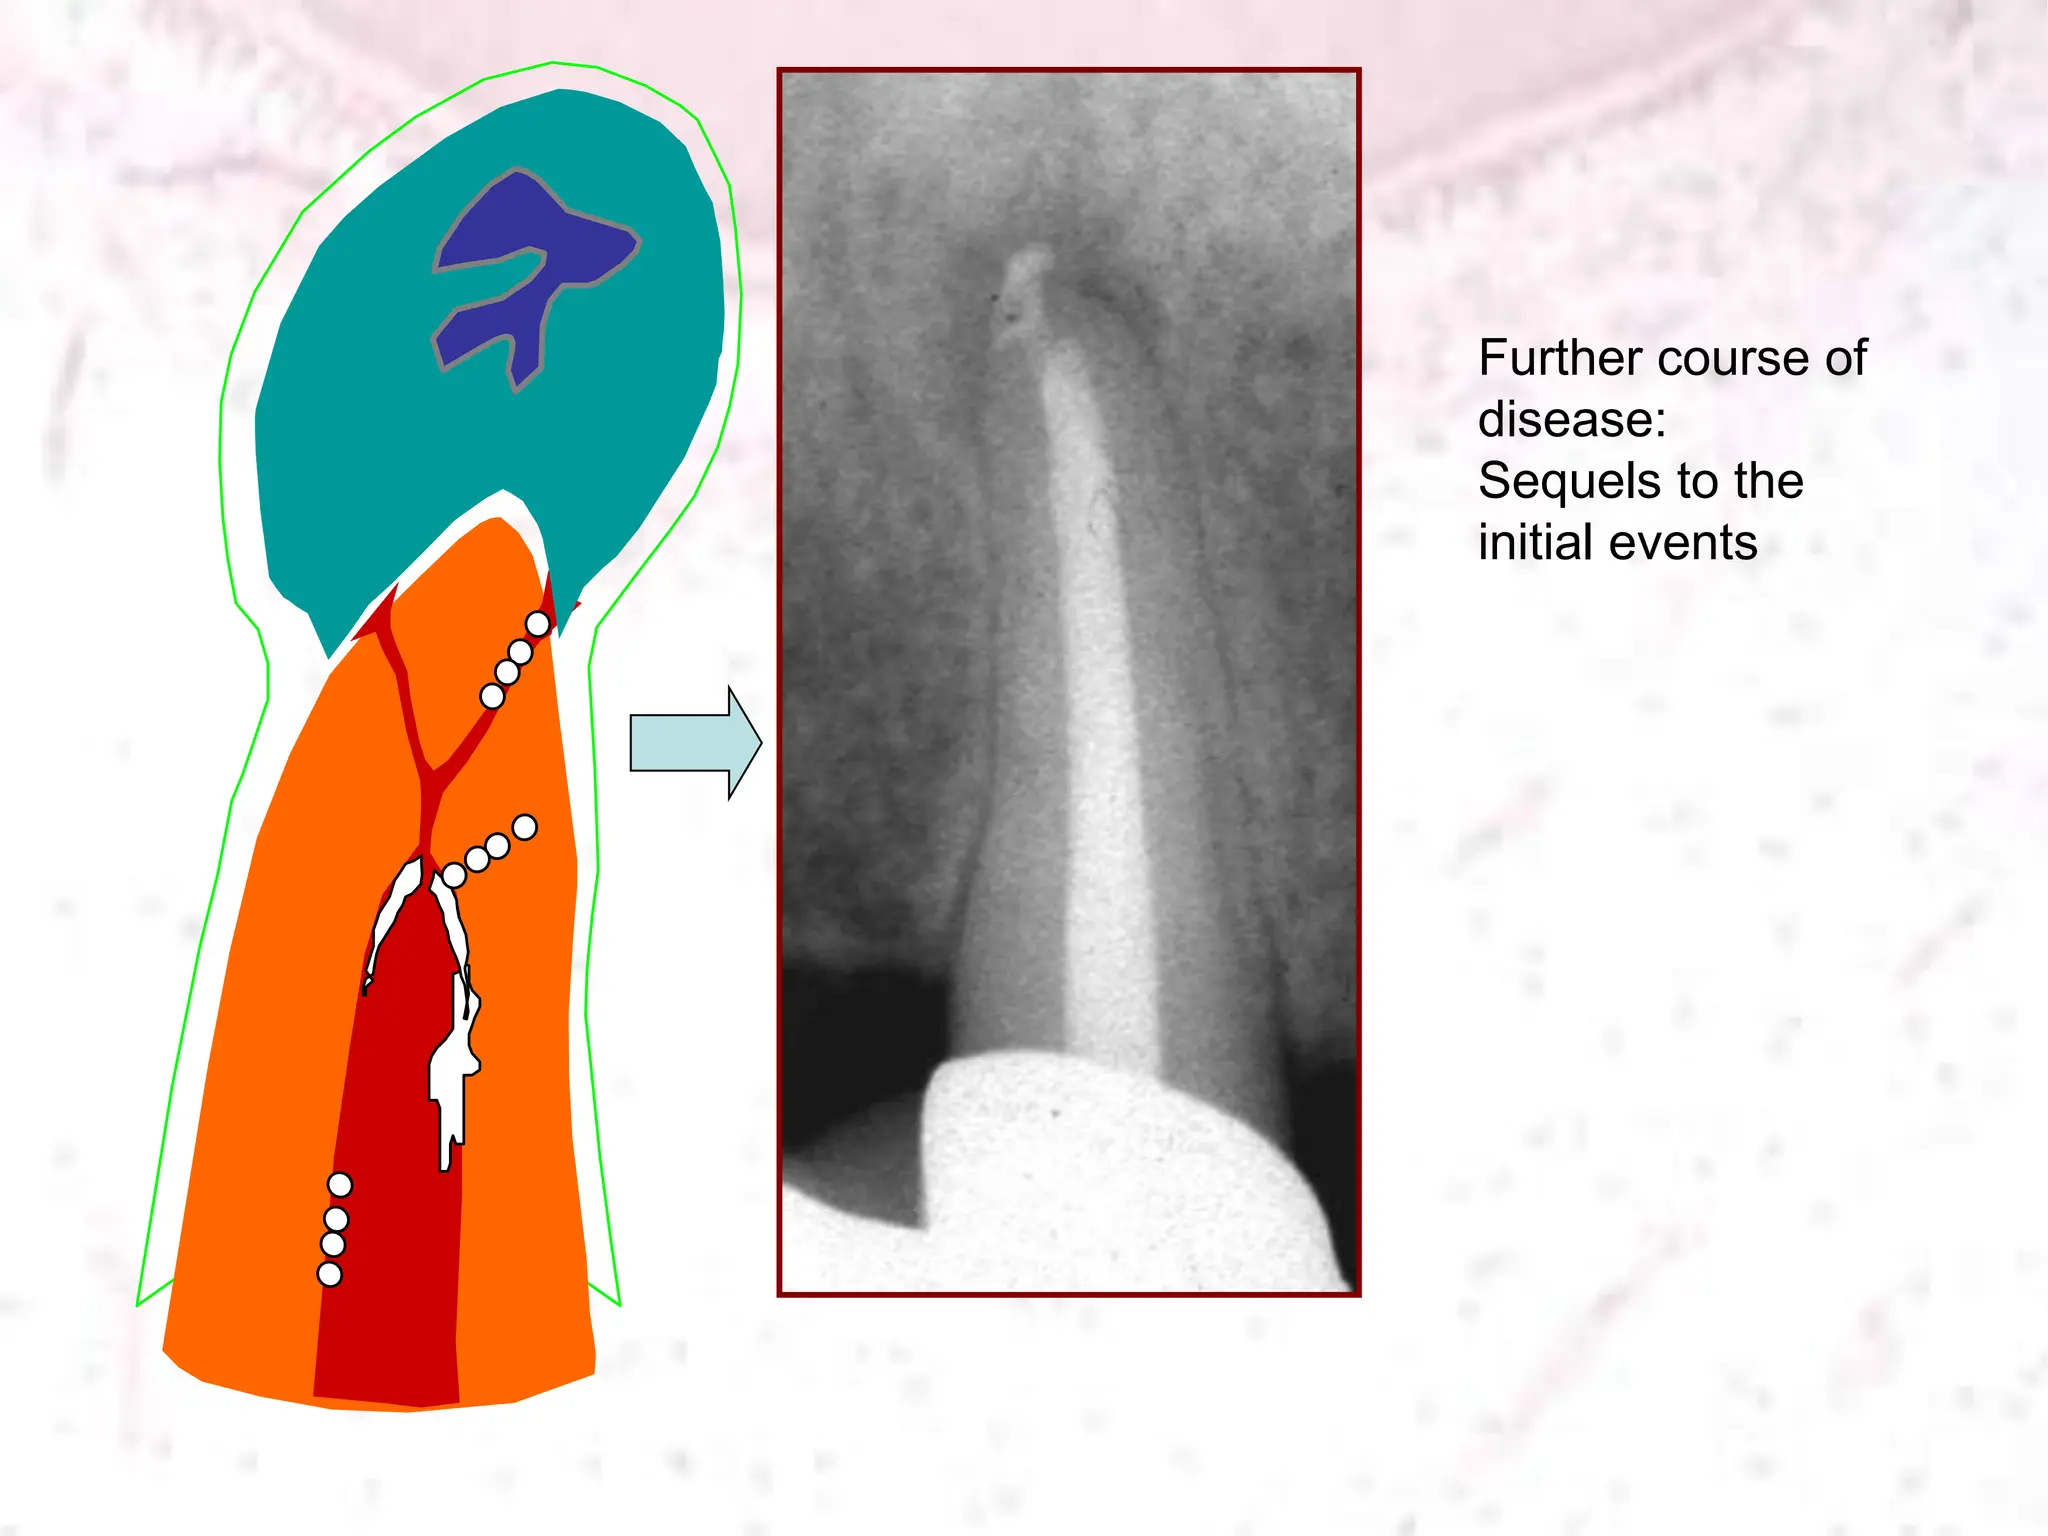

Pulpitis Necrosis

Canal

infection

Apical

periodontitis

Time

Spread to

apex

Increasing infectious load;

increasingly difficult to treat

Further course of

disease:

Sequels to the

initial events

Severity

Incidence Adielsson et al 1999